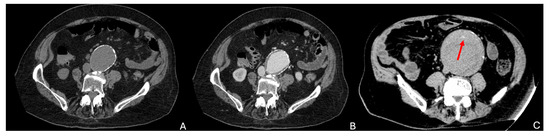

8.2. Inflammatory Aneurysm

8.3. Genetic Syndromes

| Inflammatory | Affects younger males (50–65 years), often heavy smokers | Unknown etiology; suspected autoimmune response | - Abdominal, back, or flank pain, weight loss - Elevated inflammatory markers | - Periaortic soft tissue, retroperitoneal fibrosis - 18FDG PET: Identifies inflammatory activity |

| Genetic | - Younger patients < 60 years with connective tissue disorders - Positive family history | Caused by genetic mutations | - Higher rupture risk at smaller diameters - Features like joint hypermobility, skin elasticity | - CTA: Tortuous vessels, aneurysm with thin walls - MRA: Preferred in patients needing lifetime imaging to avoid radiation exposure |